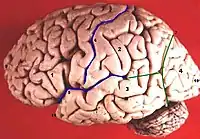

La incisura preoccipital de Meynert (incisura praeoccipitalis) es un surco que une el lóbulo occipital y el lóbulo temporal. Está considerada un punto de referencia en el cerebro ya que el lóbulo occipital está localizado justo detrás de la línea que conecta la incisura con el surco parieto occipital.

Aparece como una pequeña muesca en la porción posterior del lóbulo temporal inferior. Está situado aproximadamente a 5 centímetros delante del polo occipital, en el borde infero-lateral.

Preoccipital Muesca (mostrado en rojo)